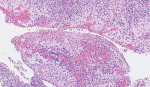

An oral surgeon reviewed the case and recommended an incisional biopsy, which was completed under local anesthesia. Using a small mucoperiosteal envelope flap for access, crestal bone was removed and sufficient lesional tissue was obtained for histological analysis. The lesion was histologically determined to be comprised of a fibrous connective tissue wall lined by a non-keratinized stratified squamous epithelium, containing acute and chronic inflammatory infiltrate (Figure 5). Based on the combined clinical, histological, and radiographic findings, and considering the anatomical site, a diagnosis of BBC was made with the recommendation for the complete surgical enucleation of the cyst. This was subsequently completed (Figure 6 through Figure 8), and an allogeneic bone graft was placed into the defect. Postoperative healing was evaluated at a 2-week interval with no complications.

The histology of a BBC can be summarized as a fluid-filled cavity lined by hyperplastic non-keratinized stratified squamous epithelium.5,12 The cyst wall can be of variable thickness, composed of fibrous connective tissue containing a chronic inflammatory cell infiltrate of lymphocytes, plasma cells, and neutrophils.4,17 The pathogenesis of the cyst lining has been postulated as arising from the proliferation of reduced enamel epithelium or the rests of Malassez of the periodontal ligament.6,13 The stimulus for the proliferation of the epithelium is a local inflammation of the periodontiumcaused by plaque, or a blockage caused by food accumulation leading to increased pressure and inflammation within the periodontal pocket.7-10